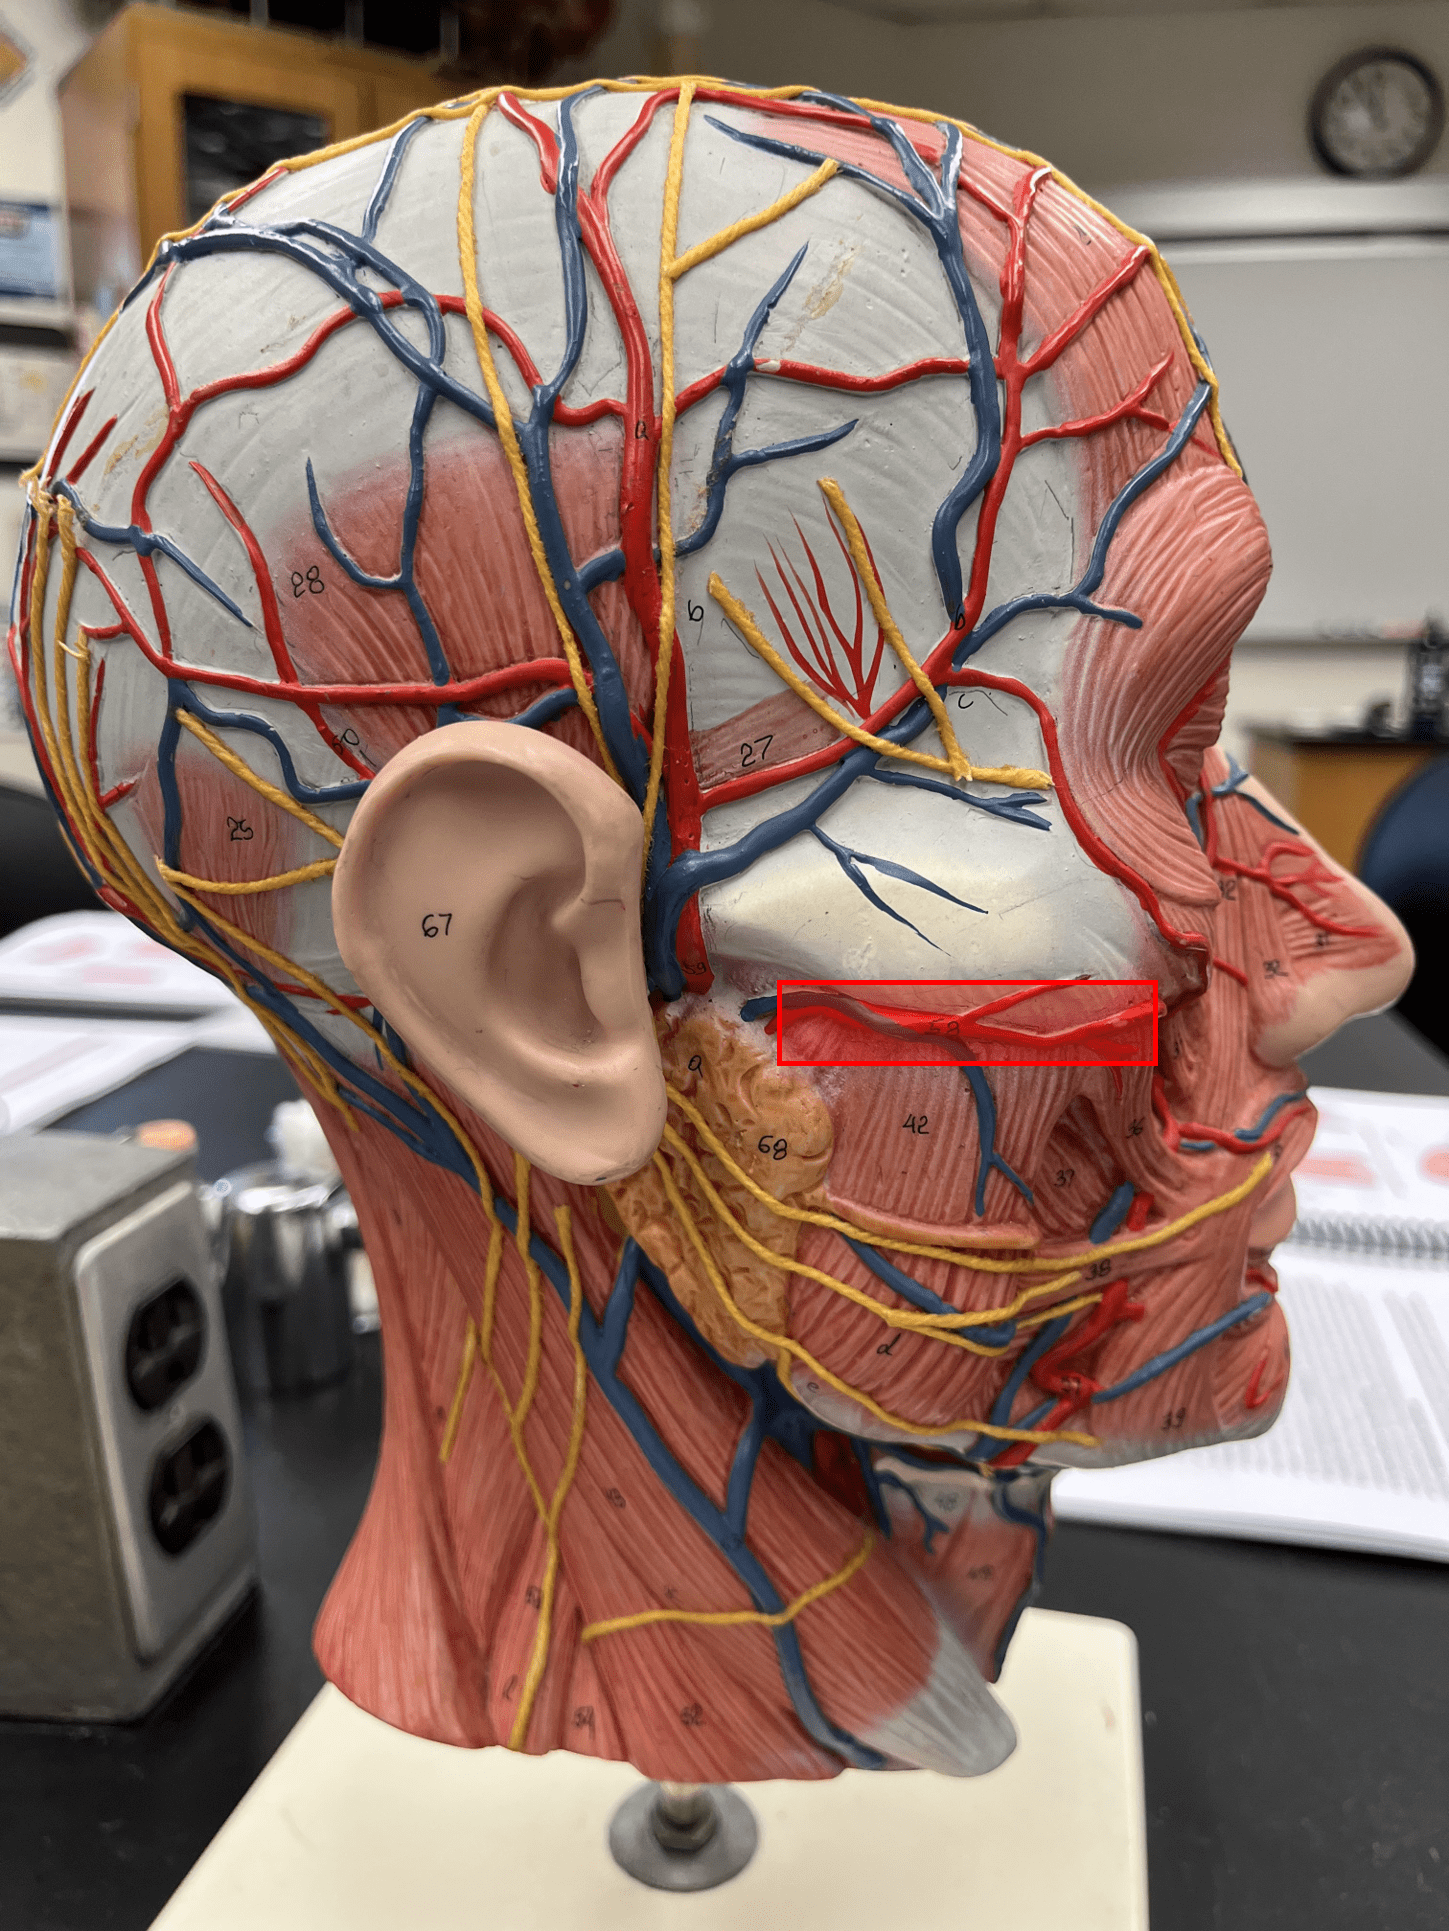

maxillary artery

• An artery of the head and neck.

• Originates from the external carotid artery.

• Supplies the teeth, maxilla, oral cavity, and external ear.

• Originates from the external carotid artery.

• Supplies the teeth, maxilla, oral cavity, and external ear.